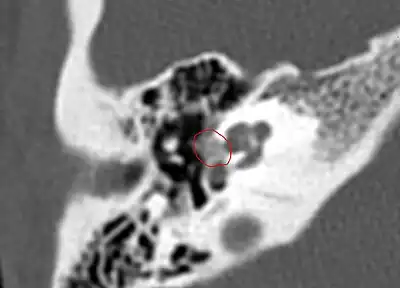

CT scan of otosclerotic focus in the anterior footplate

Imaging is usually not pursued in those with uncomplicated conductive hearing loss and characteristic clinical findings. Those with only conductive hearing loss are often treated medically or with surgery without imaging. The diagnosis may be unclear clinically in cases of sensorineural or mixed hearing loss and may become apparent only on imaging. Therefore, imaging is often performed when the hearing loss is sensorineural or mixed.

A high-resolution CT shows very subtle bone findings. However, CT is usually not needed prior to surgery.

Otosclerosis on CT can be graded using the grading system suggested by Symons and Fanning.[16]

- Grade 1, solely fenestral;

- Grade 2, patchy localized cochlear disease (with or without fenestral involvement) to either the basal cochlear turn (grade 2A), or the middle/apical turns (grade 2B), or both the basal turn and the middle/apical turns (grade 2C); and

- Grade 3, diffuse confluent cochlear involvement (with or without fenestral involvement)